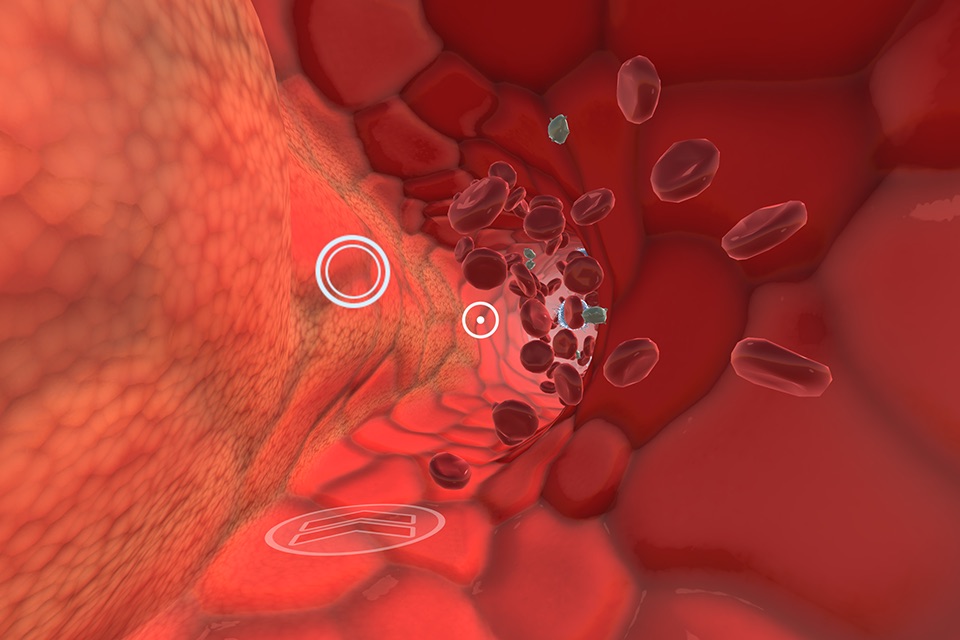

The INVIVO Bloodstream and CNS Explorer is a virtual reality experience designed for Touchscreens and Google Cardboard.

The combination of INVIVO’s world-class 3D content and technical expertise has created a virtual environment like no other. An immersive educational experience, Bloodstream and CNS Explorer transports you to the interior of a blood vessel or into the CNS to learn about human anatomy from an impossible viewpoint.